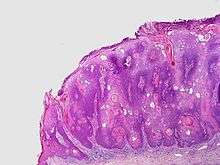

Inverted follicular keratosis is a skin condition characterized by asymptomatic, firm, white–tan to pink papules[1] and considered as a subtype of seborrheic keratosis.[2]

Microscopically, inverted follicular keratosis is characterized as a well-circumscribed inverted acanthotic squamous proliferation containing squamous eddies and without significant atypia.[3]